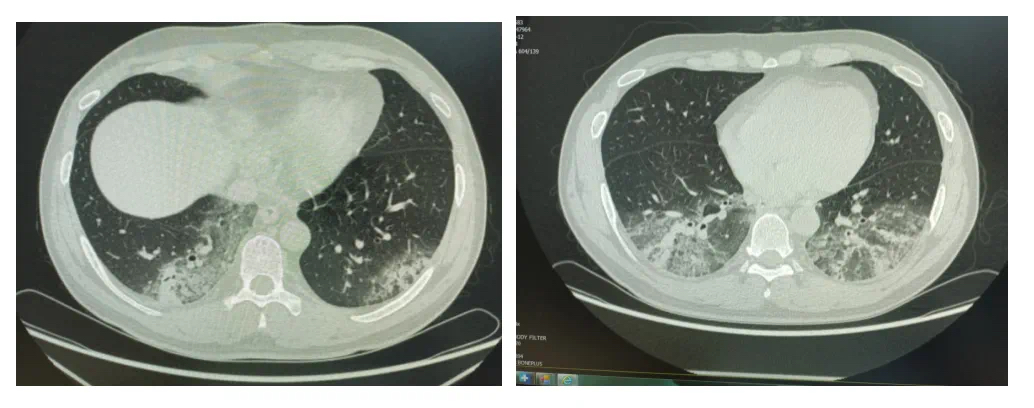

周敏介绍,该院此前也有收治此类患者。一名37岁的男士,感冒后发热咳嗽咯痰6天,入院后患者持续发热,伴头晕头痛,恶心呕吐,自己服用感冒药无效。检查中发现,患者的肺部存在严重感染,多项感染指标明显升高。入院后予以强广谱抗细菌药治疗效果不理想,患者病情迅速进展,进一步检查后,明确诊断为军团菌肺炎。

病因追溯中,患者回忆起病前曾在单位附近的篮球运动后,使用了久置未开的空调,随后出现感冒症状并逐渐加重。

患者胸部CT可见病灶扩大